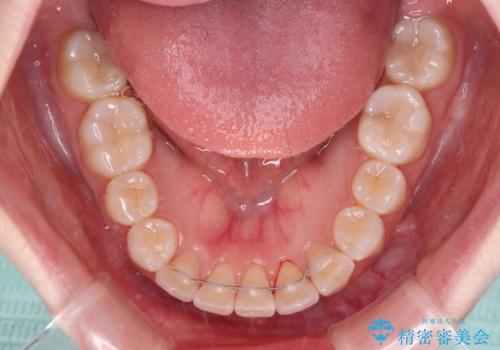

- 上下前歯のデコボコを気にして来院された患者様です。

ワイヤー矯正でもインビザライン矯正でも対応可能でしたが、インビザラインでの自己管理の煩わしさを避けるため、ワイヤー装置にて矯正治療を行うこととしました。

患者様も驚く、僅か10か月での治療終了となりました。

下顎前歯が1歯欠損しているため、上下正中は合わず、左右奥歯の咬み合わせは理想的とはならない仕上がりとなります。